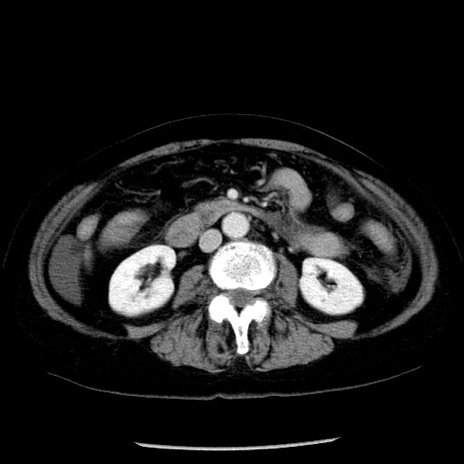

症例13(横断像)

冠状断像

【症例】70歳代女性

【主訴】腹痛、嘔吐

【現病歴】15時間程前(昨晩)より腹痛あり。今朝になっても症状の改善なく、嘔吐あり。腹痛も増悪あり、救急外来受診。

【既往歴】子宮癌全摘術後

【身体所見】意識清明、BP 121/72mmHg、P 74bpm、SpO2 100%(RA)、腹部:平坦・軟、腸雑音ほぼ聴取せず。下腹部・心窩部・臍左上に圧痛あり。反跳痛なし。

【データ】WBC 10600、CRP 0.15